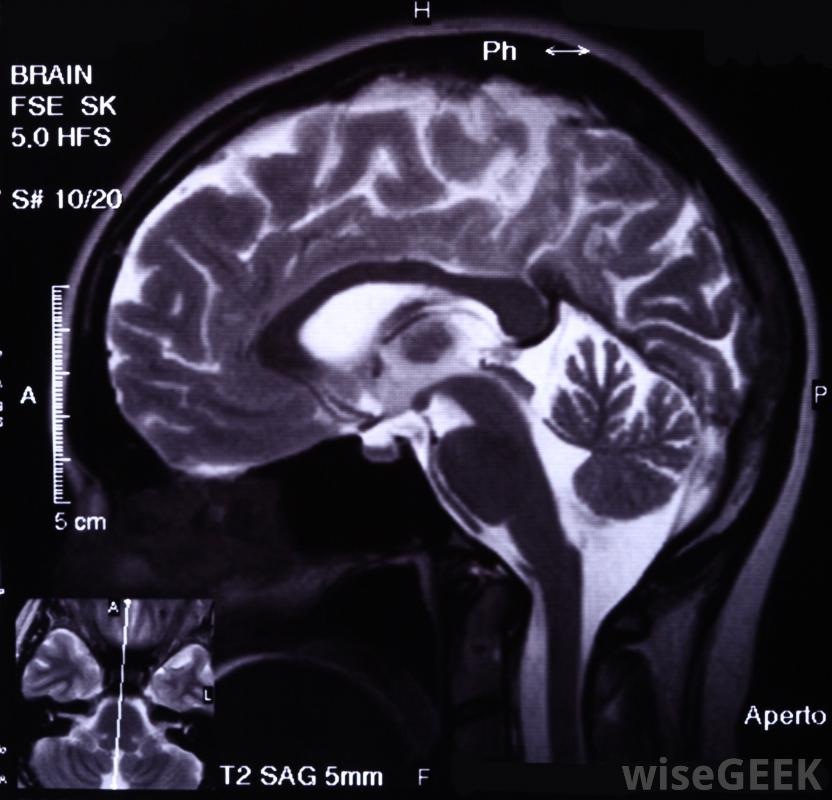

当大脑的某一部分过度兴奋或大脑中的神经开始以不正常的方式一起工作时,就会发生癫痫发作。癫痫发作可能发生在大脑中因先天缺陷或遗传疾病而畸形的区域,或因感染、伤害、肿瘤、中风而中断的区域,或氧合不足。癫痫发作的病理生理学是由于刺激和抑制神经细胞的力之间突然失衡,从而使兴奋性的力量占上风。这种电信号随后传播到周围的正常脑细胞,在短时间内癫痫发作持续或反复发作,随着神经细胞死亡,瘢痕组织形成,未来癫痫发作的风险增加,CT扫描可以用来调查病人癫痫发作的原因放电之间的神经细胞通常在内部带有负电荷,这是由于正电荷的钠离子从细胞中主动泵出。神经细胞的放电或放电会使负电荷突然波动到正电荷,因为离子通道进入细胞,而正离子如钠离子,钾和钙流入细胞。兴奋性和抑制性控制机制都起作用,允许适当的放电和防止细胞的不适当的兴奋。癫痫的病理生理学可能是由于神经细胞的兴奋性增加,神经细胞的抑制性降低,或两者的影响的结合